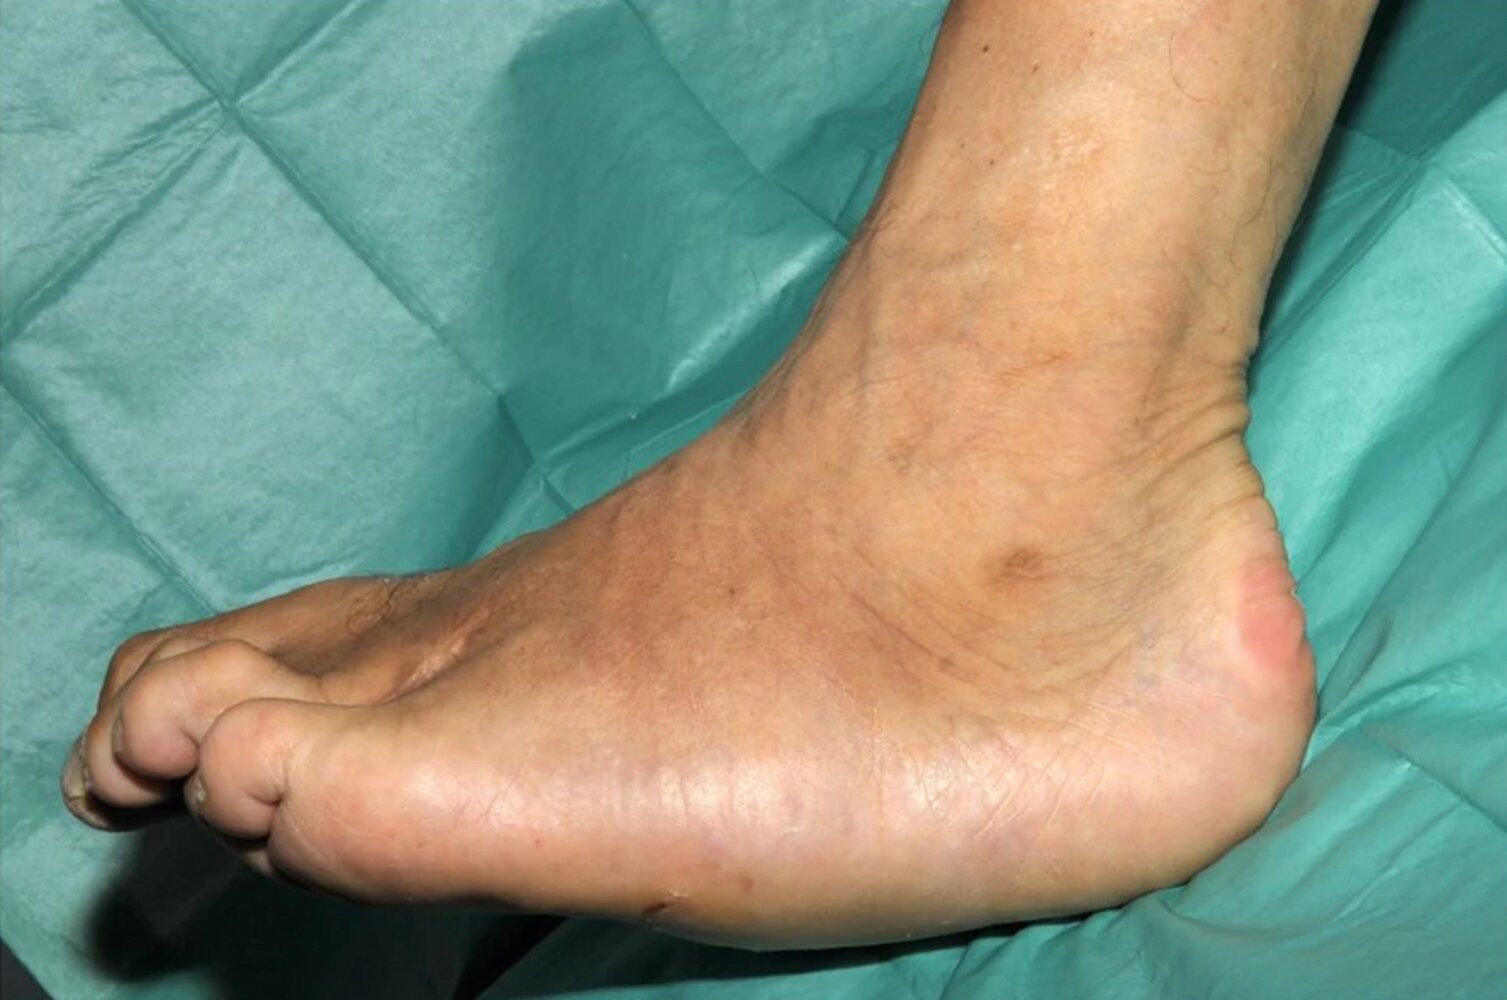

Diabetic neuropathic arthropathy (Charcot foot) [14]

• Neuropathic arthropathy is the development of bone destruction, subluxation/dislocation, and deformity secondary to neuropathy (most commonly diabetic neuropathy).

• The tarsus and tarsometatarsal joints are most commonly affected.

• Clinical presentation depends on the stage.

• Acute stage

• Swelling, warmth, erythema

• Pain is typically mild-to-moderate, as the underlying peripheral neuropathy reduces sensation.

• Chronic stage: painless bony deformities, midfoot collapse (rocker-bottom foot deformity), osteolysis, fractures

• Diagnosis requires x-ray (first line) and MRI (in diagnostic uncertainty).

• Initial treatment is conservative (mechanical offloading, treatment of diabetes); surgery is used for severe or refractory cases.